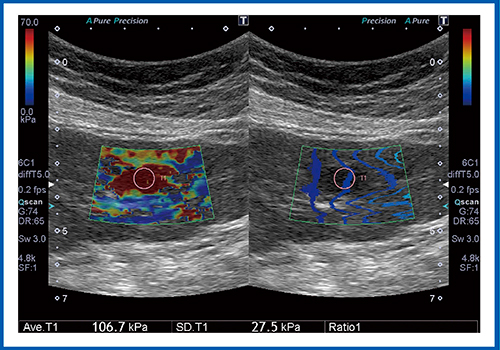

図7は,大腸がんの肝転移症例である。本症例は肝臓の大部分にわたる占居性病変(SOL)であり,弾性率は173.4kPaと,非常に硬い値を示した。

図7 大腸がんの肝転移のSWE